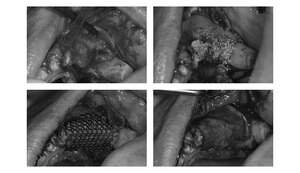

【担当医師所見】

コーンビームCT像を確認すると左側上顎の骨は無くインプラント埋入の際は上顎骨に骨造成が必要と思われたため上顎洞挙上術(サイナスリフト)を併用、インプラント埋入を行うプランとしました。

また欠損部位の大きさを考えるとサージカルガイドの使用が必要と思われたため今回使用した。さらにオペの強度を考え静脈内鎮静法下にてオペを行った。

処置前では黒い透過像(骨が無い)があるが骨造成後1年経過、インプラントテック(仮歯)を入れた際では上顎洞内及びインプラント周囲に白い不透過像(骨がある)が確認できます。